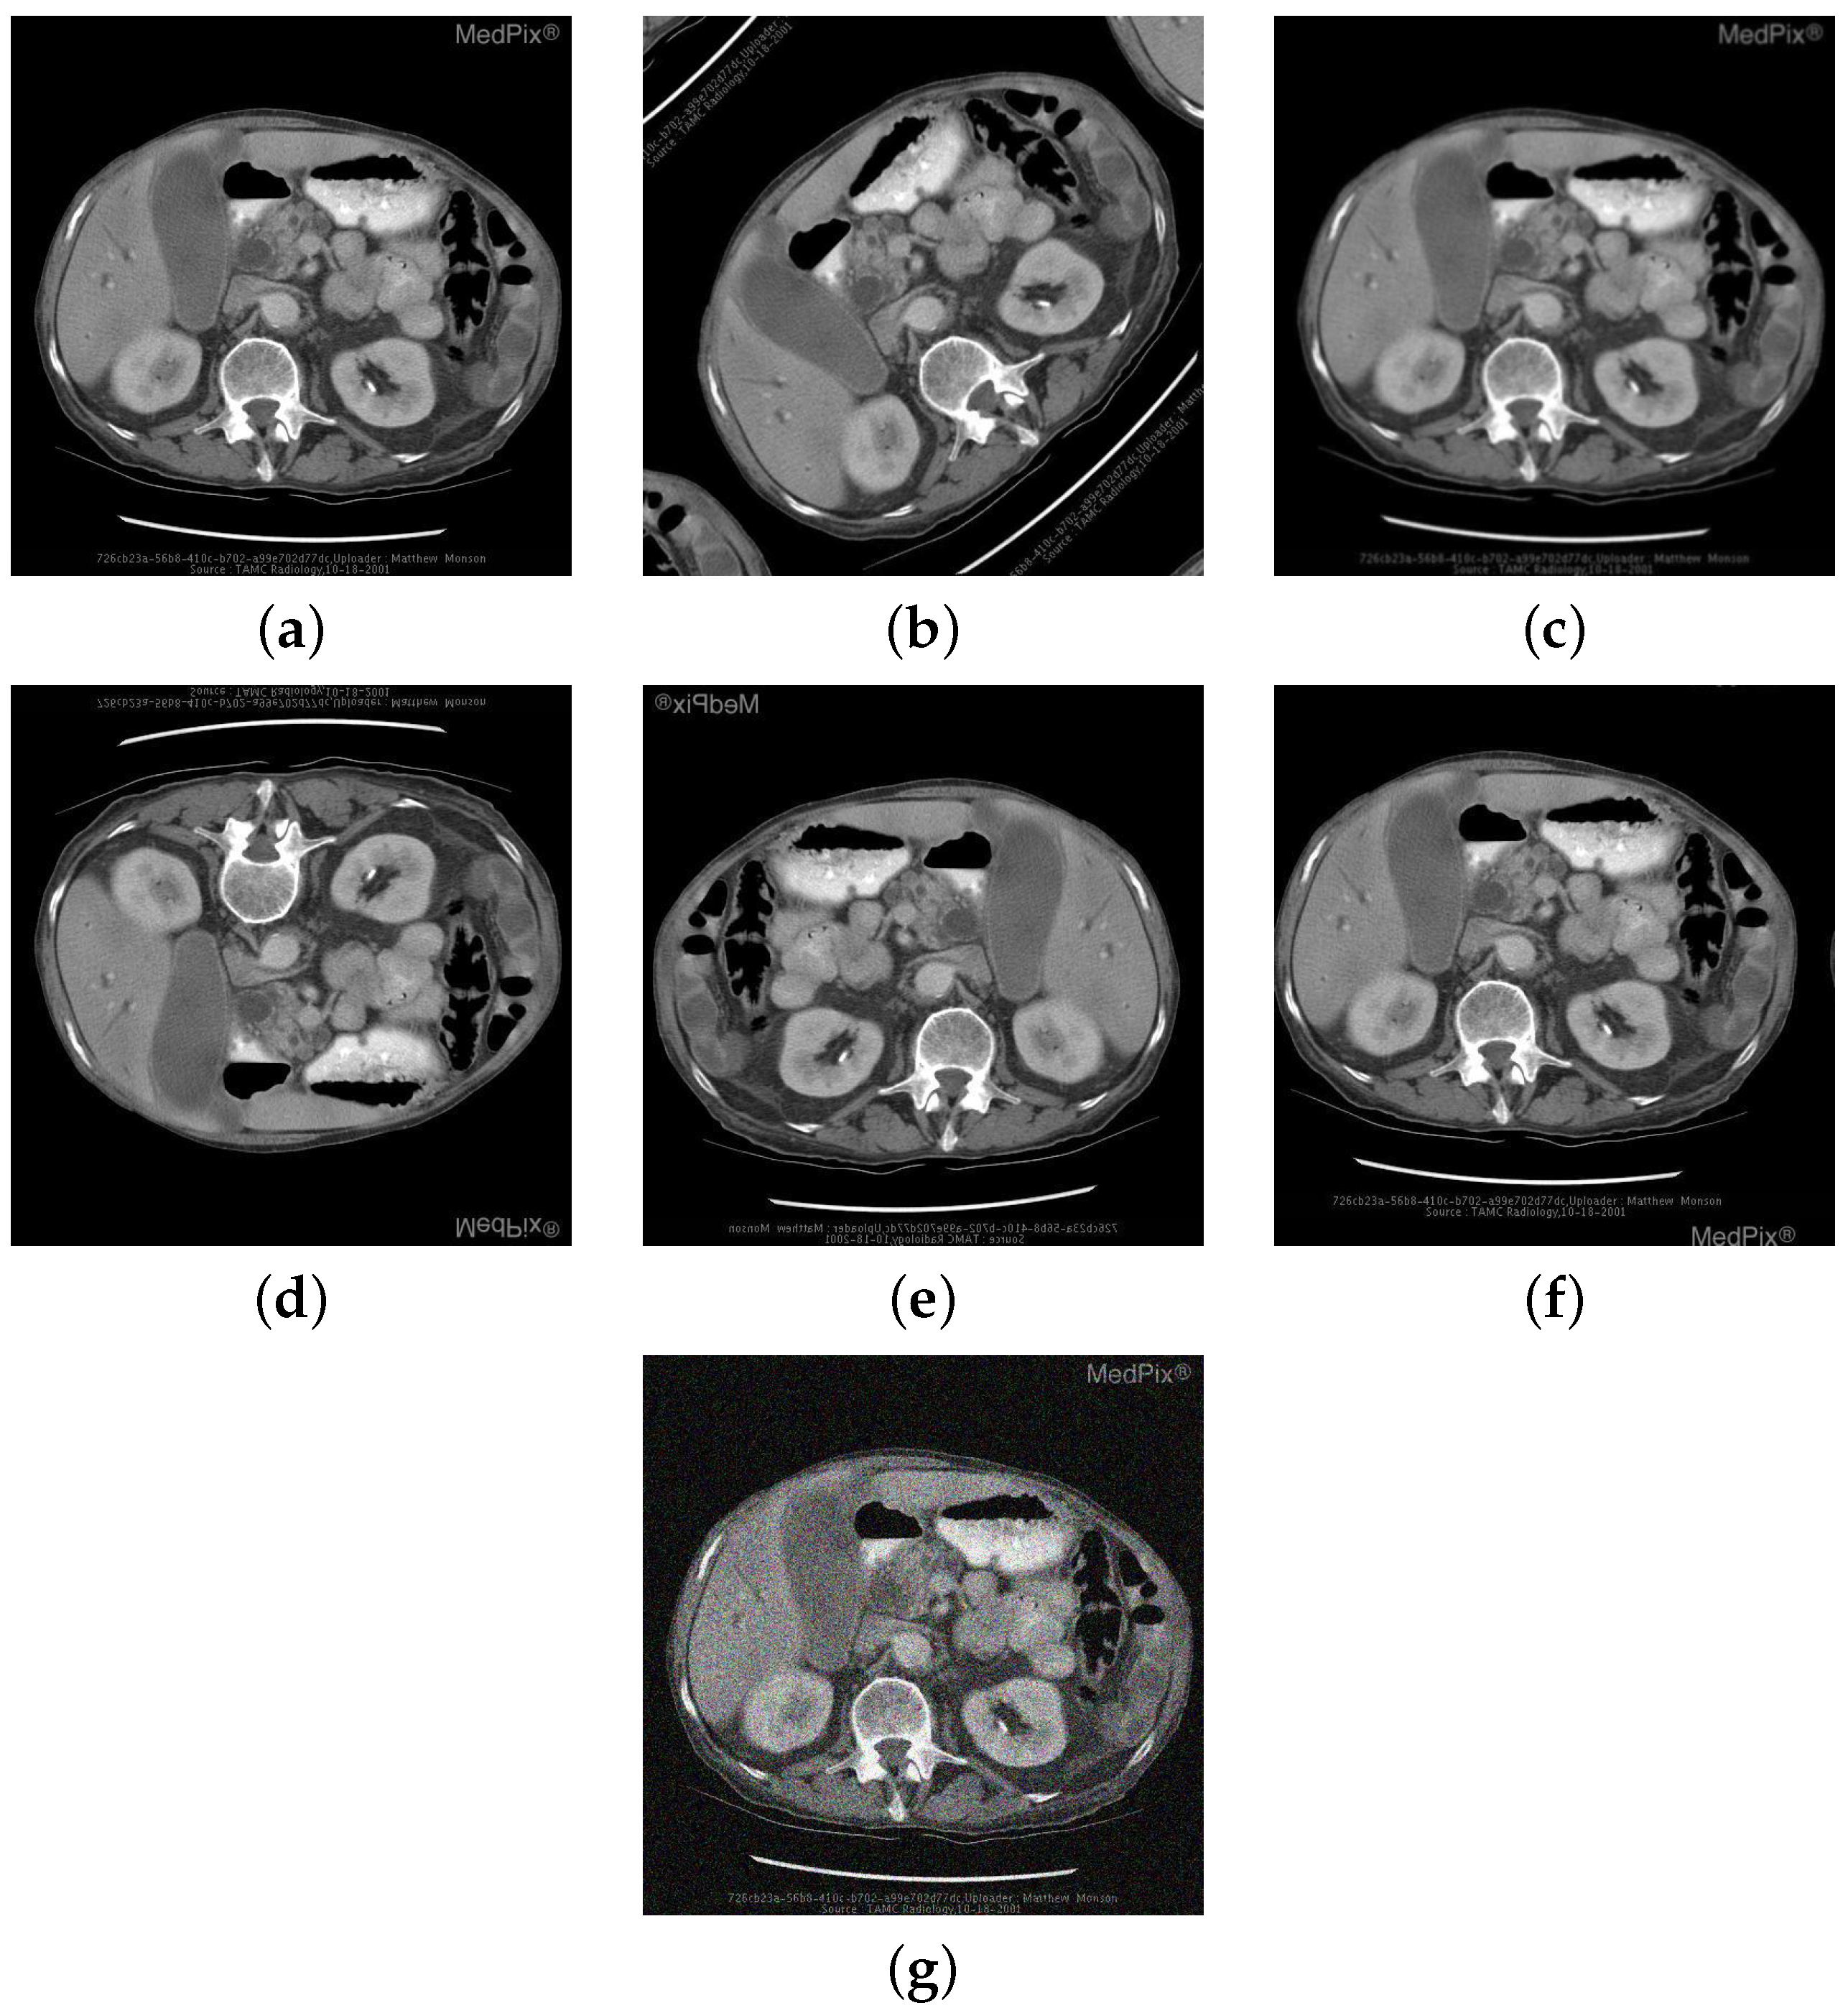

| Image | Category | Generated and Ground Truth Questions |

|---|---|---|

![]() | Abnormality | is a ring enhancing lesion present in the right lobe of the liver? is a ring enhancing lesion present in the right lobe of the liver? is the liver normal? |

![]() | Organ | is this a typical liver? are these normal laughed kidneys? Is this a study of the brain? |

![]() | Plane | what plane is this image obtained? what plane is this image blood-samples? Is this image of a saggital plane? |